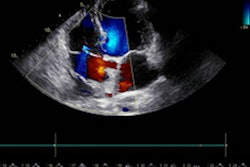

Echocardiography links lower left atrial function -- as opposed to the size of the left atrium -- to an increased risk of dementia later in life, according to research published March 22 in JAMA.

Left atrial function, though not size, on echo exams could be considered a risk factor pending more evidence, wrote a team led by Wendy Wang, a doctoral student in epidemiology from the University of Minnesota.

Alterations in size and function for the left atrium, also known as atrial myopathy, lead to myriad heart problems. However, not much is known about atrial myopathy's effects on dementia. The researchers wrote that the link is possible since lower left atrial reservoir function is linked to the presence of silent brain infarcts and white-matter hyperintensities.

Wang et al wanted to use echocardiographic measures of left atrial function and size and see if the association with incident dementia exists. They also wanted to quantify the contribution of atrial function to previous associations.